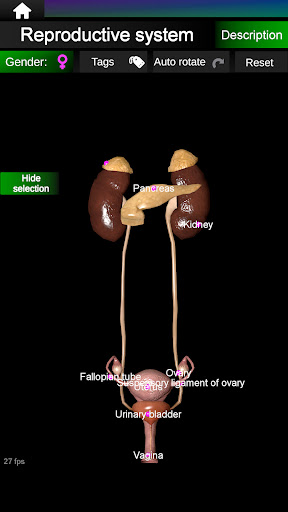

* Репродуктивна система, яка включає чоловічі та жіночі репродуктивні органи.

* Порівняйте чоловічі та жіночі органи.